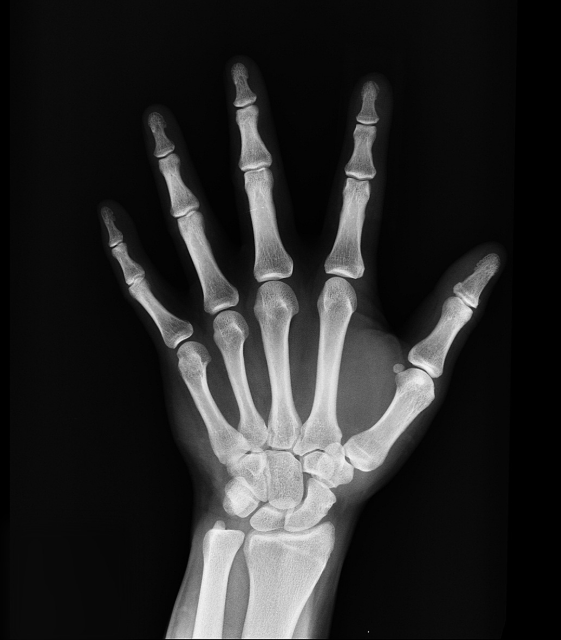

성장판검사는 손목이나 손의 뼈를 X-ray로 촬영한 뒤, 뼈의 성숙도를 분석하여 ‘골연령’을 확인하는 검사입니다.

골연령은 실제 나이와 다를 수 있습니다. 예를 들어 만 10세이지만 골연령이 12세라면 성장판이 빨리 닫힐 가능성이 있고, 반대로 골연령이 8세라면 성장 여력이 더 남아 있을 수 있습니다.

골연령을 통해 예측 키를 계산하기도 하며, 사춘기 진행 속도를 간접적으로 파악하는 데도 활용됩니다.